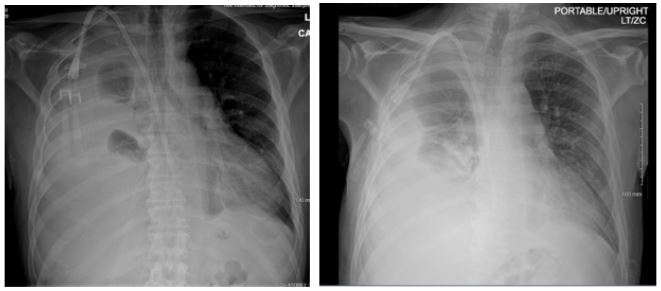

Patient presented with elevated blood pressure at 174/88. BMP was significant for Na 133, K 4.6, BUN 29, Cr 5.3. CMP is significant for Albumin 2.5. CBC was significant for Hb 8.7, Hct 25.0. D-dimer was found elevated at 4,670. PT and INR were normal. ABG significant for pH 7.52, pCO2 31.4, HCO3 25.3. A chest x-ray on admission demonstrated a large right-sided pleural effusion, contributing to significant compressive atelectasis of the right lung and leftward deviation of the mediastinal structures. Thoracentesis was performed, which demonstrated blood- tinged serosanguinous fluid. Transthoracic echocardiogram demonstrated EF 60-65%, LV diastolic dysfunction, with trace mitral and tricuspid regurgitation, and was negative for pericardial effusion. CT Chest demonstrated a large volume right-sided pleural effusion without pneumothorax, with extensive progressive atelectasis throughout the right lung. There was also a trace left-sided pleural effusion and pleural thickening with round atelectasis in the posterior left lower lobe, as well as minimal interstitial edema in the left lung. A chest tube was placed with consistent drainage throughout admission. Repeat chest x-rays continued to demonstrate pleural effusion. Thoracotomy, decortication, and pleurodesis were performed with Video-Assisted Thoracoscopic Surgery (VATS), with significant improvement of symptoms. The pleural fluid biopsy was negative for malignancy and revealed fibrocollagenous tissue with chronic inflammation and a few reactive epithelial cells. Thorough review of the patient’s medication list led to suspicion that the patient’s 50 mg Hydralazine three times a day may be the offending agent. Anti-histone antibody titers were found to be elevated at 3.7. Free Kappa and Lambda light chains were elevated. Antinuclear Antibody (ANA) titers were found to be negative. Hydralazine was discontinued, and after chest tube removal and improved chest x-ray, the patient was discharged home. It was recommended that the patient follow up with their primary care provider and rheumatologist.

Figure 1: Chest radiographs demonstrating large right sided pleural effusion, and small left lower pleural effusion.